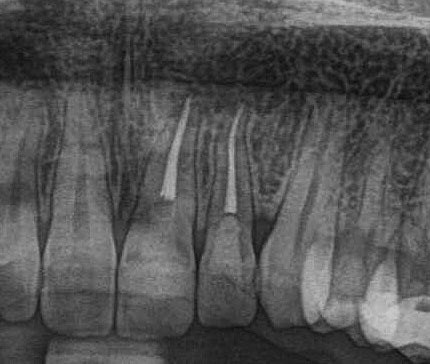

#kist#kanaltedavisi kök çevresinde görülen kist kanal tedavisi ile iyileştirildi herkes mutlu